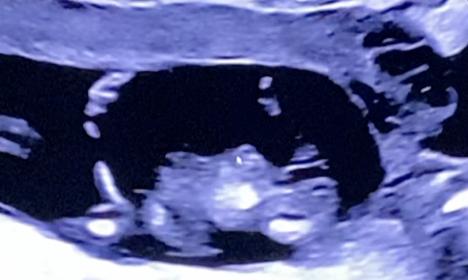

Tricky NUB 13+1 weeks? Long NUB but some stacking?

I had a scan yesterday (13+1 weeks!). During the scan I was convinced I saw long somewhat flat, but also a stacked nub (I saw a shadow in the background), but the tech said it was the stacking was the umbilical cord. The tech said she saw a flat NUB that I is why she was leaning more towards girl.

I posted my scans online and got mostly boy guesses (some girl because of the "flat" NUB) but I was wondering if it's still possible it might be a girl? That the "stacked thing" is something else??? (Already got 3 boys so a girl would be so welcome!)